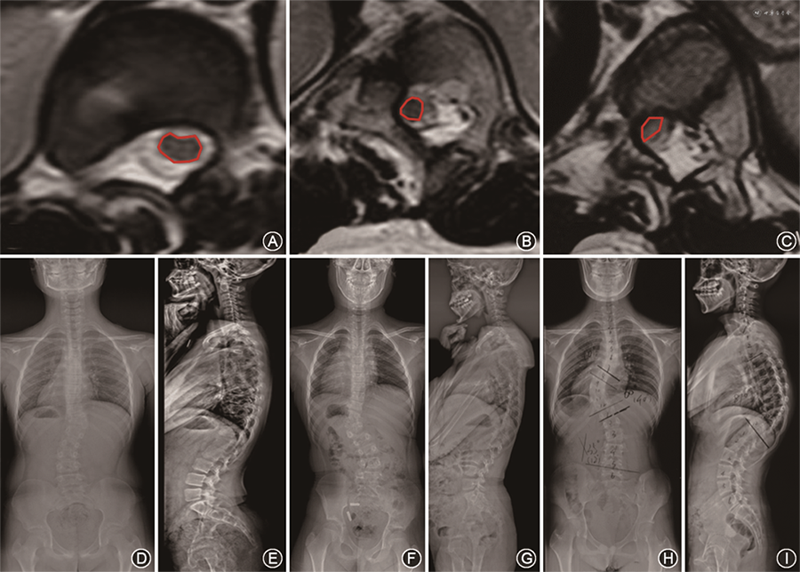

所有患者术前、术后即刻及随访时均拍摄站立位全脊柱正侧位X线片,分别测量以下冠状面和矢状面参数[7]:(1)主弯侧凸Cobb角;(2)冠状面平衡(coronal spinal balance,C7PL-CSVL);(3)最大后凸Cobb角(global kyphosis,GK);(4)矢状面平衡(sagittal vertical axis,SVA)。根据术前的全脊柱MRI检查将患者顶椎区的脊髓形态分为三型:Ⅰ型:脊髓形态光滑,外观为圆形/椭圆形且与椎弓根和(或)椎体间有可见的脑脊液;Ⅱ型:脊髓形态光滑,外观为圆形/椭圆形但与椎弓根/椎体间不存在脑脊液;Ⅲ型:脊髓受压形态扁平,脊髓和椎弓根/椎体之间不存在脑脊液(图1)。

112例患者术前顶椎区脊髓形态分型为Ⅰ型8例(7.1%)、Ⅱ型58例(51.8%)、Ⅲ型46例(41.1%)。所有患者的末次随访时间为(28.5±3.4)个月。与术前相比,3组患者术后主弯侧凸Cobb角、C7PL-CSVL、GK、SVA均有显著矫正,手术前后差异均有统计学意义(均P<0.05),末次随访时与术后即刻差异均无统计学意义(均P>0.05),均无矫正丢失。3例术前脊髓形态为Ⅱ型的患者术后出现新发神经损害,Frankel分级均为D级;6例术前脊髓形态为Ⅲ型的患者术后出现新发神经损害,Frankel分级为C级1例、D级5例;3例术前脊髓形态为Ⅲ型的患者出现已有神经功能损害加重,Frankel分级均由术前的D级加重至C级。脊髓形态为Ⅲ型的患者术后新发神经损害或已有神经损害加重的发生率比Ⅱ型患者更高(19.6%比5.2%,P=0.037)。

112例患者中,共105例患者术前神经系统查体未见明显神经损害,14例患者术前合并下肢神经功能损害,包括Ⅱ型5例、Ⅲ型9例(术前Frankel分级均为D级)。3例(3/58)术前脊髓形态为Ⅱ型的患者术后出现新发神经损害,Frankel分级均为D级,末次随访改善至E级;6例(6/46)术前脊髓形态为Ⅲ型的患者术后出现新发神经损害,Frankel分级为C级1例、D级5例,末次随访时Frankel分级为D级2例、E级4例;3例(3/46)术前脊髓形态为Ⅲ型的患者术后出现已有神经功能损害加重,Frankel分级均由术前的D级加重至C级,末次随访时分别改善至D级1例、E级2例。与术前脊髓形态为Ⅱ型的患者相比,Ⅲ型患者具有更高的术后新发神经损害或已有神经损害加重的发生率(19.6%比5.2%,χ²=6.589,P=0.037)。